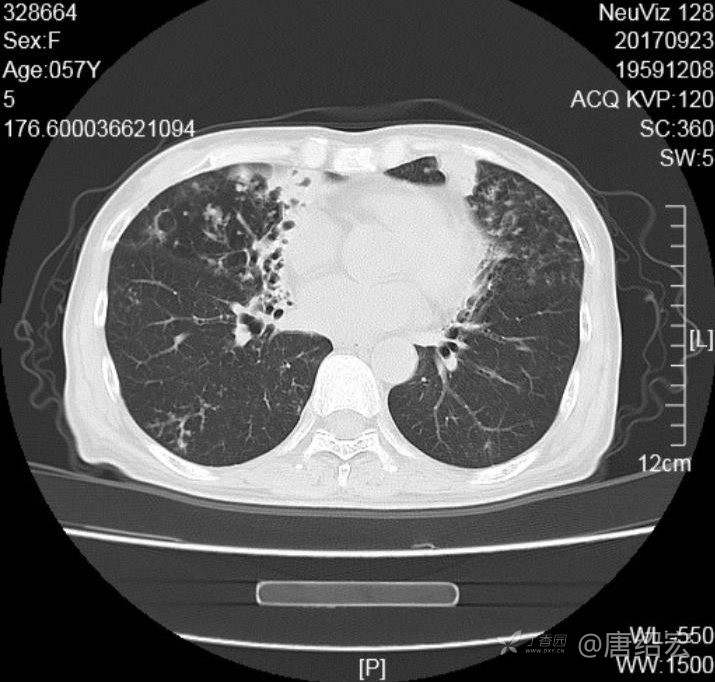

中年女性满肺树芽征还有支气管扩张,考虑什么疾病?

女,57岁,

主诉:发热、咳嗽、咯黄痰,胸闷3天入院。

铜绿假单胞菌性肺炎 (12)

铜绿假单胞菌感染 (20)